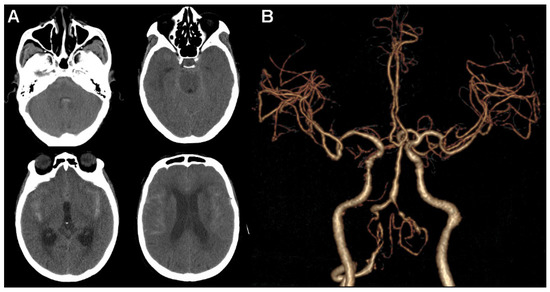

2. Case Presentation